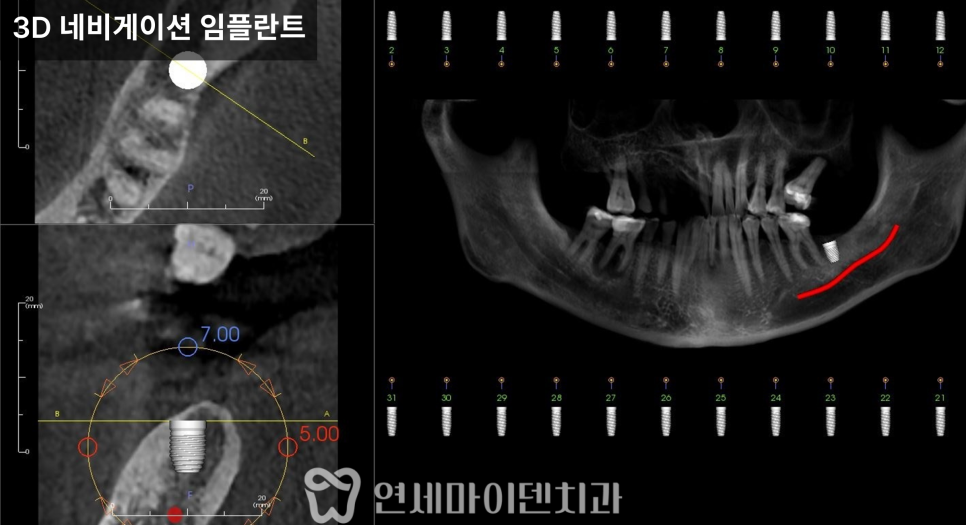

또한 아래턱은 하치조 신경관이 지나가는 부위이기 때문에

CT를 통해 정확한 위치를 계획한 뒤

발치와 동시에 임플란트를 식립했습니다.